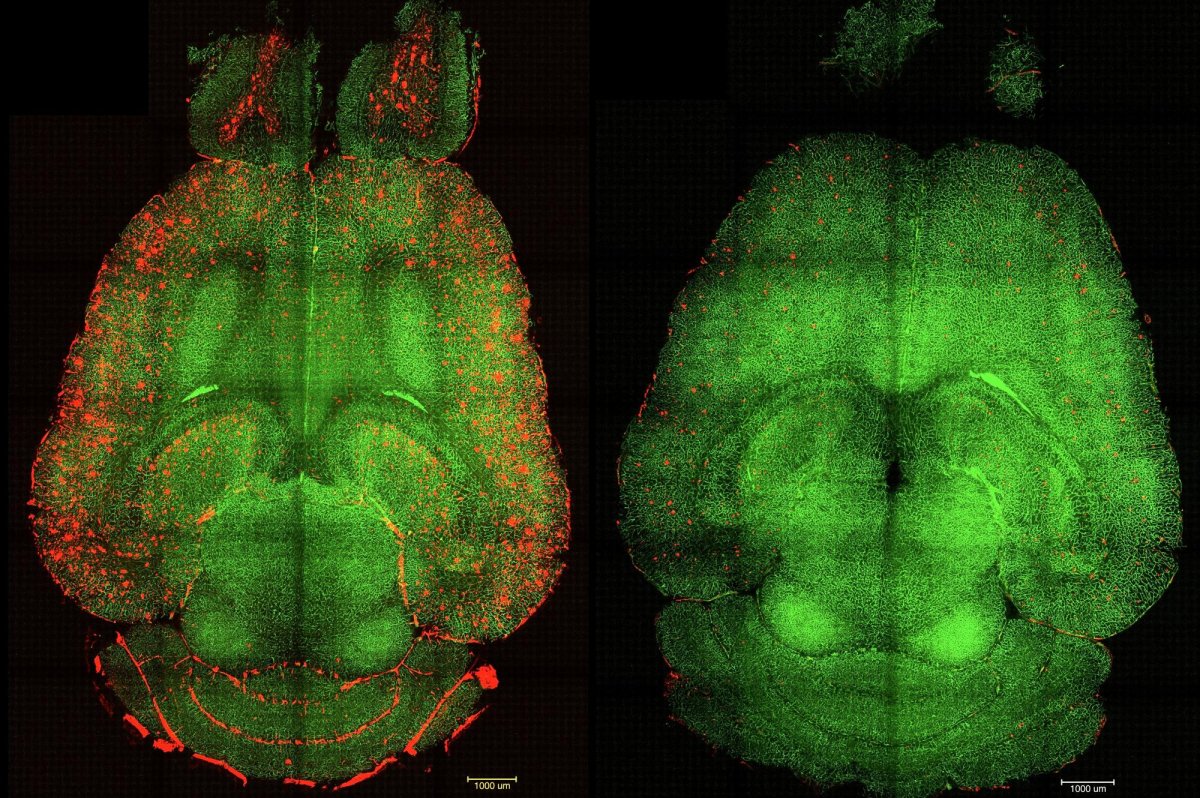

Synaptic proteins degrade more slowly in aged mice than in younger mice, a new study finds. Microglia appear to unburden the neurons of the excess proteins, but that accumulation may turn toxic, the findings suggest.